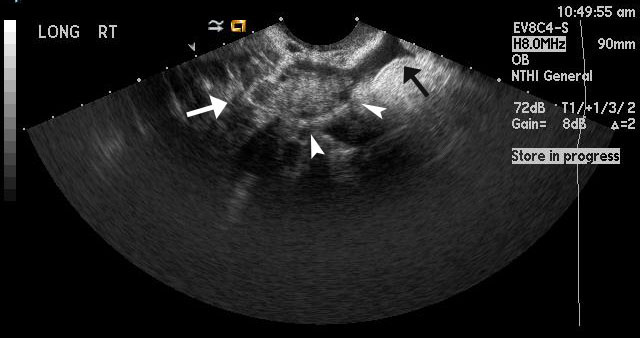

Figure 3

Magnified image shows the ectopic pregnancy in the left adnexa with the arrow pointing towards a fluid filled gestational sac that is anechoic. The calipers are measuring a hyperechoic area within the gestational sac, which most likely represents a fetal pole. |

Figure 7

For comparison, this image shows a normal right ovary. The white arrow points towards the ovary. The arrowheads point towards hypoechoic round structures, which represent normal follicles. The black arrow indicates a small amount of physiologic, anechoic free fluid, (no echogenicity or complexity). |